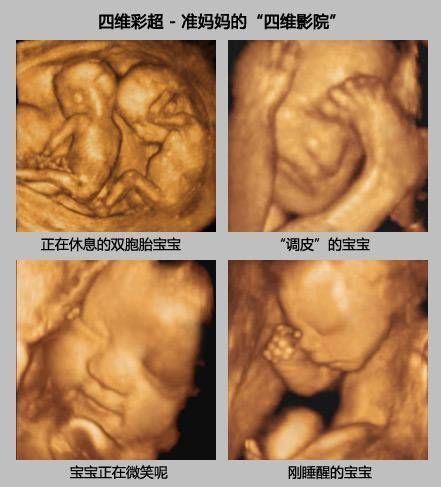

孕期产检,相信不少孕妈妈都很期待四维排畸这一项了,四维彩超排畸检查有不少准妈妈也想带着准爸爸进去,一同分享这其中的喜悦。

【 医生|为什么有些医院做四维彩超不让家属陪同这些原因,大家有权知道】小茹怀孕24周左右的时候,身边朋友提醒她这个时候需要做四维大排畸了,不仅能知道胎宝宝发育状况,还可以提前看到宝宝的长相。